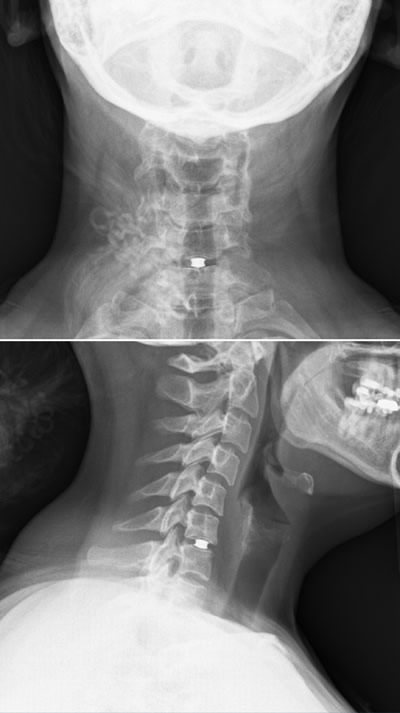

Van Kort’s herniated disc causing debilitating pain.

Van Kort had a herniated disk between C6 and C7. With the severity of the pain and weakness, Dr. Jenkins quickly worked her into his surgery schedule. Weeks prior to relocating to a new city, she was relieved after meeting Dr. Jenkins. She knew she had a trusted surgeon on her side and didn’t have to search blindly in a new city for someone she could trust to do her spine surgery.

“Elizabeth presented with a problem called myeloradiculopathy from a cervical disc herniation,” said Dr. Jenkins. “This is where a disc herniation in the neck can put pressure on the spinal nerve (causing pain) and spinal cord (causing neurologic dysfunction). The unique thing about Elizabeth is how young and healthy she was at the time of presentation. She did not have a lot of arthritis or bone spurs. Therefore doing the typical spinal fusion was not a great option for her. Following FDA trial indications for cervical disc replacement, Elizabeth was a perfect candidate for a cervical disc replacement. This allowed me to solve her spinal cord and nerve root compression without fusion of her spine and preserving motion.”